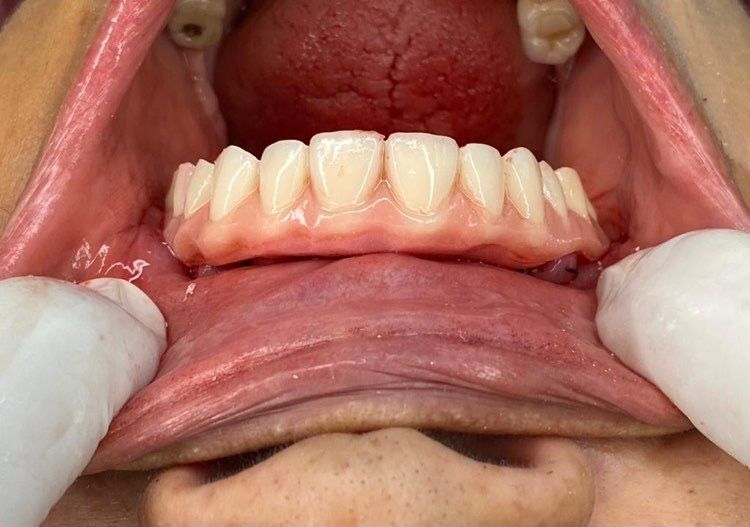

Case 005 Case: Técnica de ancoragem esquelética “All on Four STD” pelo Dr. Carlos Franza

Formado há 20 anos, o experiente Dr. Carlos Franza tem como foco de trabalho casos complexos de reabilitação total.

Atua no estado de São Paulo desde 2002 na área da implantodontia e Bucomaxilo, buscando sempre parcerias e interações de grandes profissionais da área no desenvolvimento e operacionalidade de novas técnicas buscando acima de tudo, satisfação dos pacientes.